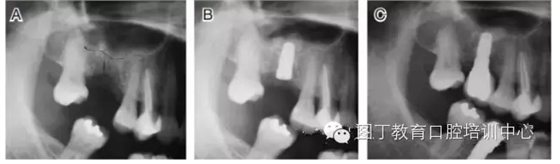

病例3 有骨間隔(圖5)

圖5